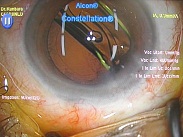

黄斑円孔の手術に関しては、?で記載しましたが、簡単におさらいすると、目の中に器械をいれて、内境界膜という網膜の表層の膜を剥離し、網膜を柔らかくします。その後、目の中に空気を入れてうつ伏せをすることで、円孔の周囲の網膜を浮力で引き寄せて、穴を閉じる。という方法です。

ここで重要なのですが、手術は、

なくなってしまった中心部(黄斑部)の網膜を元に戻すのではありません。

周りの網膜を引き寄せて、穴を閉じ、中心部の網膜の代役をさせるのです。